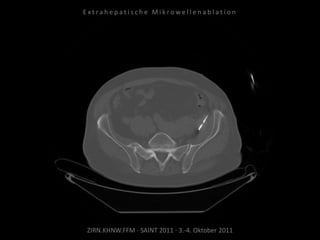

Metastase medial des linken

Musculus iliacus:

1 Nadelposition.